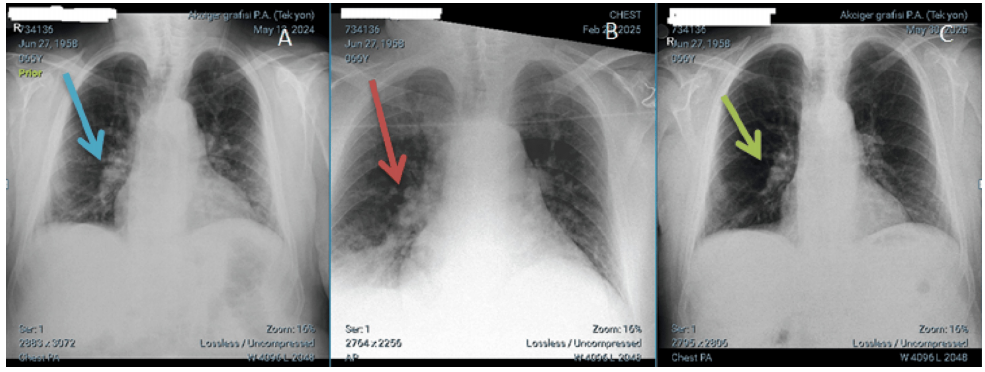

由于未发现超容量表现,初步诊断为“肾前性急性肾损伤”,予静脉补液1500 ml/d。图1A-1C分别为患者在呼吸科门诊随访时的基线胸部X线片、入院时胸部X线片和出院后胸部X线片。

图1. 胸部X线片(A:门诊随访时;B:会诊时;C:出院时)